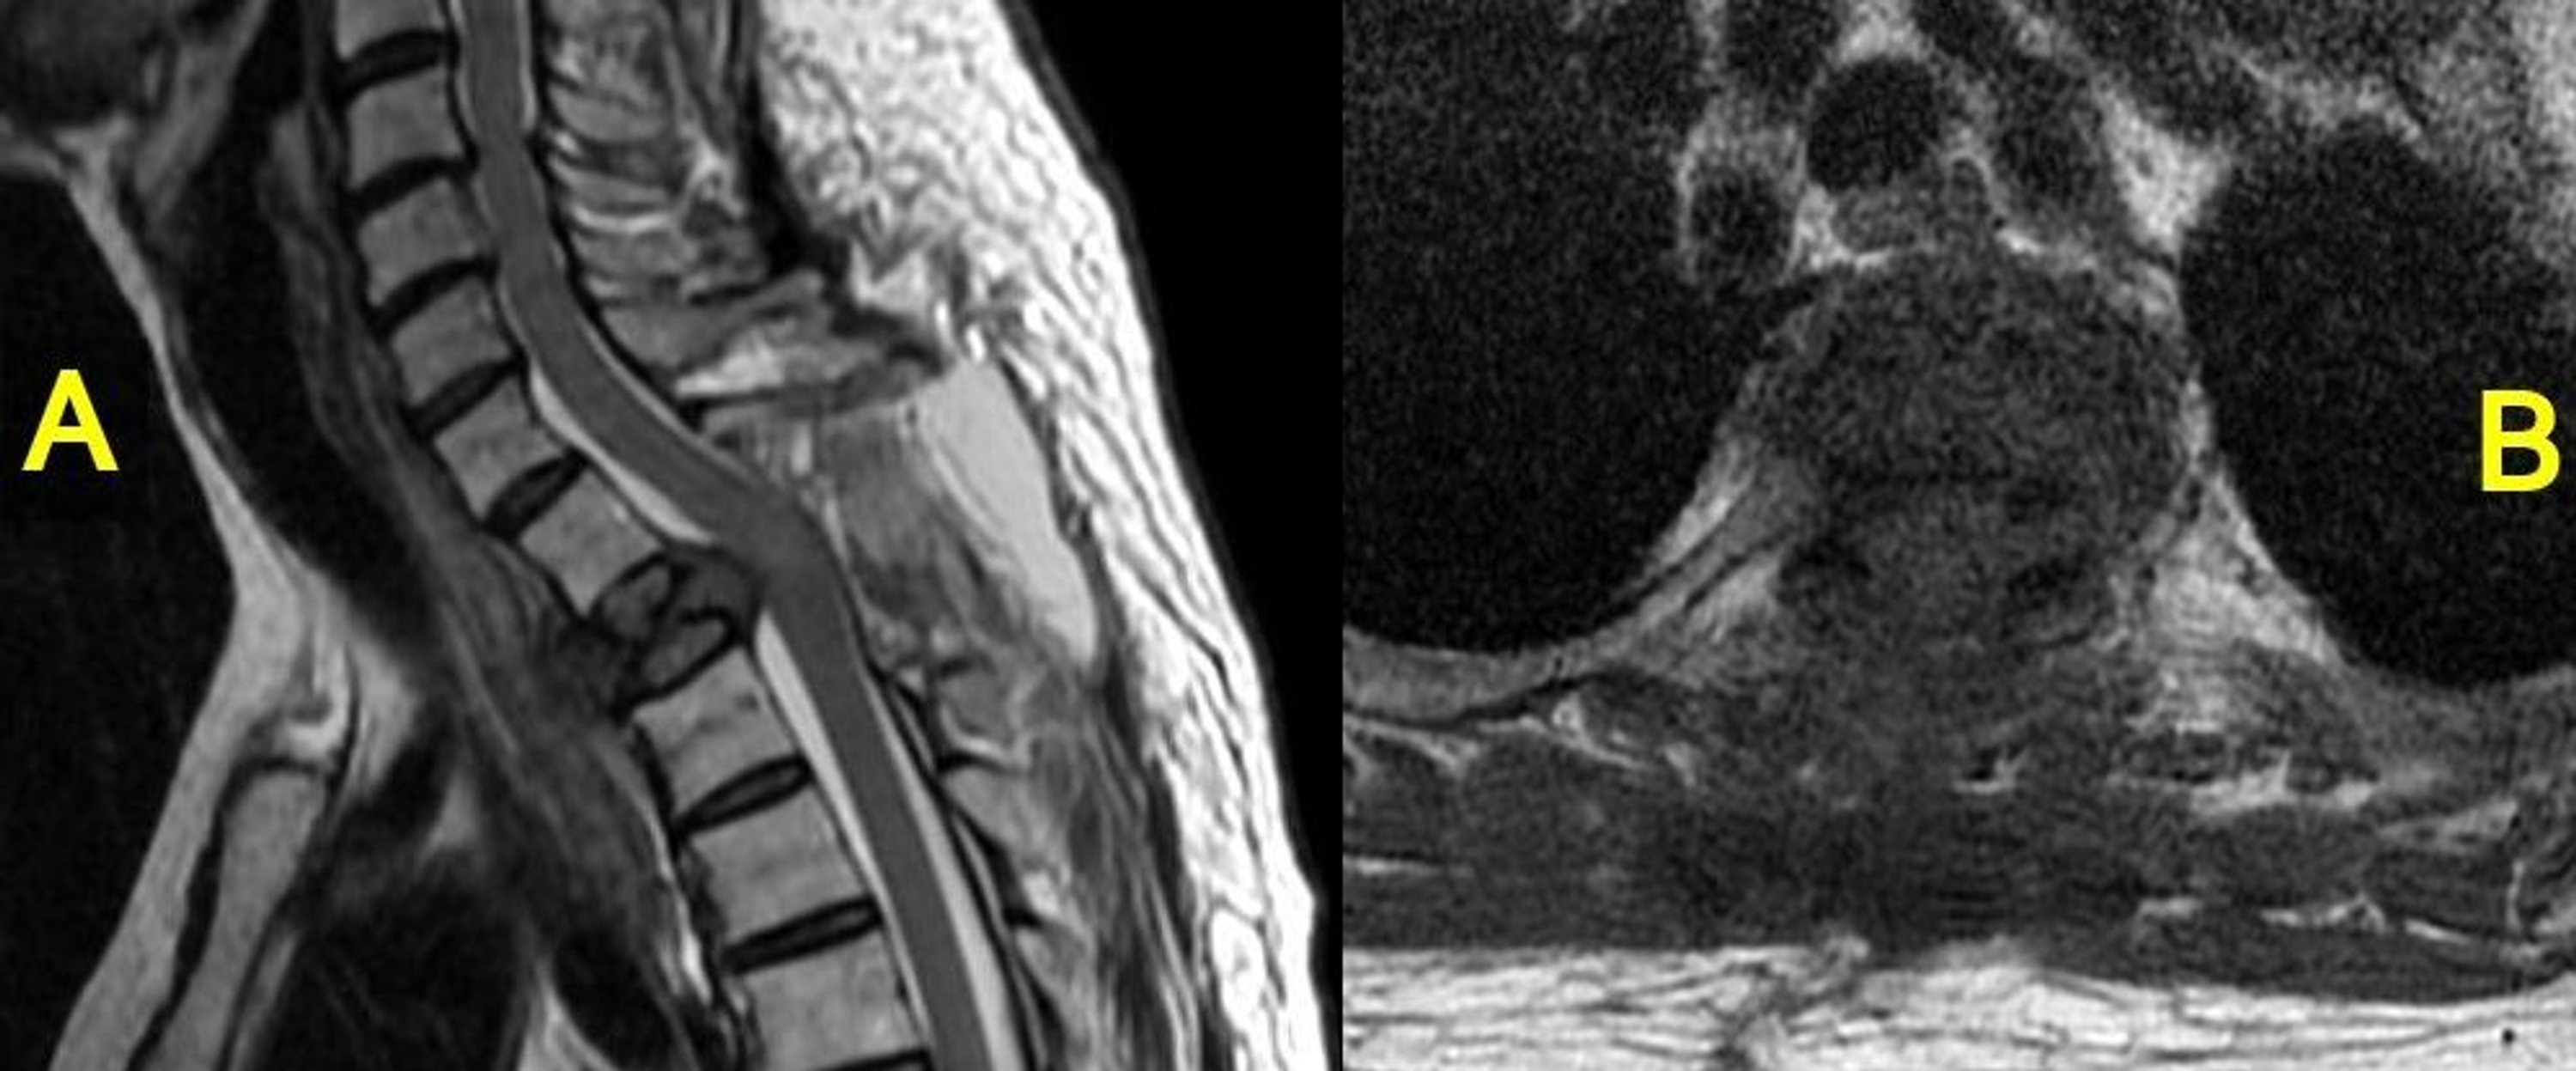

Severe spinal cord compression from epidural prostate metastases

From radiopaedia.org

Severe spinal cord compression from epidural prostate metastases Spinal Cord Compression Metastatic Prostate Cancer Outlook in patients with spinal cord compression from metastatic prostate cancer is poor. spinal cord compression (scc) in metastatic prostate cancer (mpc) is a critical complication and multiple factors. Malignant spinal cord compression (mscc) is one of the most devastating complications of cancer. osseous metastases are common in both patients with mhnpc and mcrpc [ 4, 5] and. Spinal Cord Compression Metastatic Prostate Cancer.